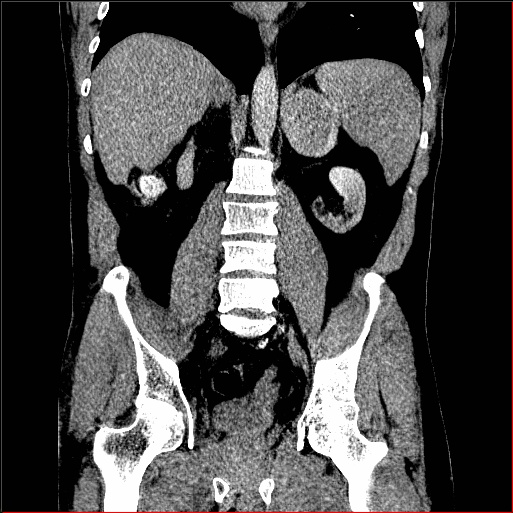

MAISI-v2 Controlnet qualitative Results:

Figure 5 shows qualitative results for MAISI-v2 Controlnet on 5 types of tumors.

Lung Tumor

0.75×0.75×0.60.75\times 0.75\times 0.6

mm

512×512×512512\times 512\times 512

Liver Tumor

0.75×0.75×0.50.75\times 0.75\times 0.5

512×512×768512\times 512\times 768

Panc. Tumor

1×1×11\times 1\times 1

Colon Tumor

0.75×0.75×1.50.75\times 0.75\times 1.5

512×512×256512\times 512\times 256

Bone-Les

1×1×1.31\times 1\times 1.3

512×512×384512\times 512\times 384

Figure 5: MAISI-v2 segmentation-guided results for five types of tumors. We show results for different voxel spacing and volume size to demonstrate the flexibility of MAISI-v2. Different Hounsfield Unit window is used to better show the contrast between tumor and normal tissues.